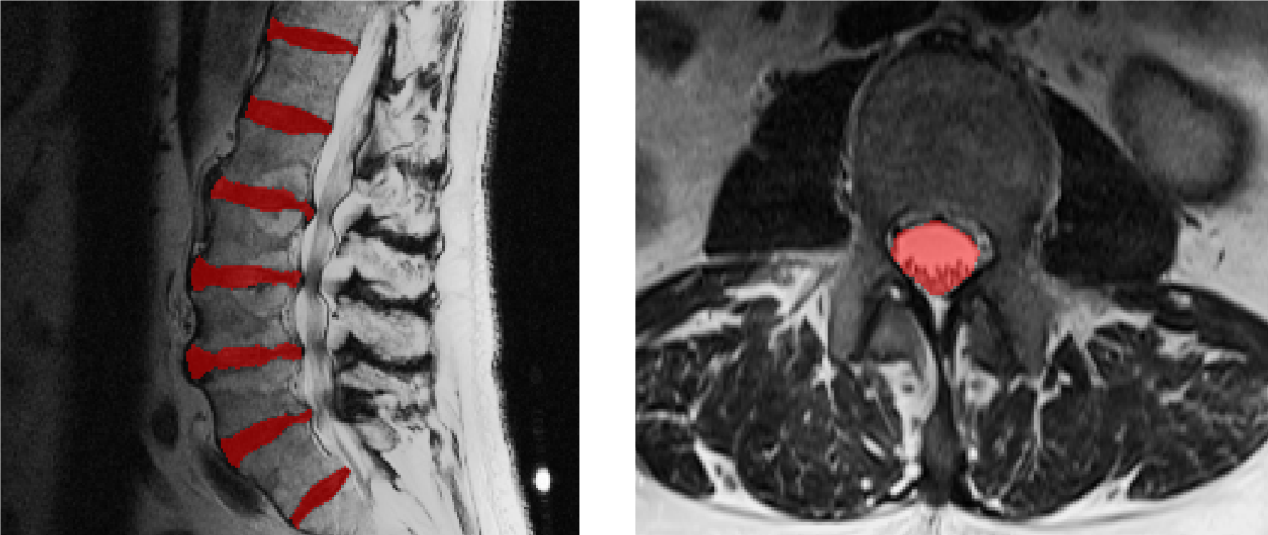

The first set of experiments used 100 axial T2-MRI scans of the lumbar spine, on which manual segmentations of the spinal canal are available. The scans used were randomly selected from a clinical imaging database. They contained artifacts due to variation in acquisition, pathology as well as metallic implants and surgical hardware often used in treating spine related conditions. We expect a robust segmentation algorithm to achieve accurate segmentation despite the presence of these artifacts. Thus, a robust algorithm will have both high average dice score and a lower standard deviation in Dice scores. The more the robustness, the better the applicability to a clinical scenario. We ran Eigenrank for 7 iterations thus choosing 21 images. We also selected 21 random images from the data in groups of 3.

Refer to caption

Figure 3: Top Row Randomly selected subjects Bottom Row Subjects selected by the first iteration of the proposed algorithm

Three, cases selected via random sampling are presented alongside for comparison. It can be seen from the figure 3 that Eigenrank selects cases which are much more complex as compared to random sampling. One of these cases has abnormally scoliotic pathology, the second has screws and the third has a relatively lower contrast, perhaps due to an acquisition issue. By contrast the variation in both intensity, pathology and instrumentation within cases picked randomly is, distinctively lower.